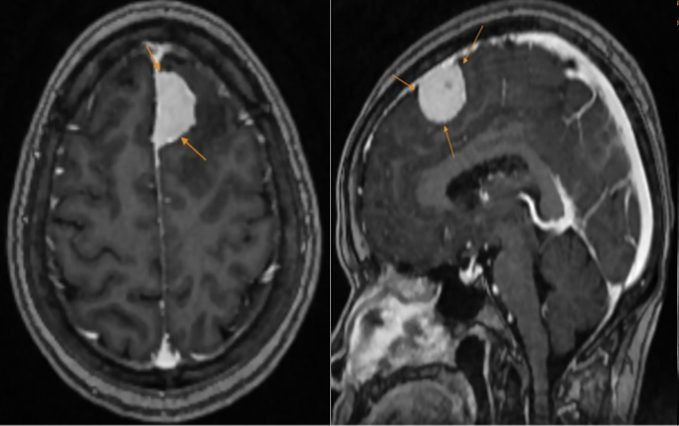

| Phim chụp của bệnh nhân. |

Kết quả MRI khiến cô H. bất ngờ khi có một khối u lớn vùng trán trái, kích thước khoảng 27x15mm, nghi ngờ u màng não. Nhờ phát hiện kịp thời, bác sỹ đã tư vấn phương án can thiệp an toàn và hiệu quả, hạn chế rủi ro biến chứng.

Ths.Lê Quỳnh Sơn, Phòng Chẩn đoán hình ảnh, Phòng khám Đa khoa MEDLATEC Cầu Giấy cho biết, MRI và CT là những phương tiện chẩn đoán hình ảnh hàng đầu trong đánh giá các tổn thương u não. Hai kỹ thuật này không chỉ xác định chính xác vị trí và kích thước khối u mà còn cung cấp cái nhìn đa chiều về mối quan hệ giữa tổn thương và các cấu trúc não xung quanh.

MRI não đặc biệt hữu ích trong việc xác định nguyên nhân các triệu chứng bất thường như chóng mặt, đau đầu kéo dài, yếu liệt cơ, suy giảm thị lực, thính lực, động kinh, xuất huyết, phù não, tổn thương não do chấn thương hoặc đột quỵ. Đặc biệt, MRI còn giúp phát hiện sớm các ổ nhồi máu não nhỏ, ngay cả khi chưa xuất hiện triệu chứng lâm sàng.